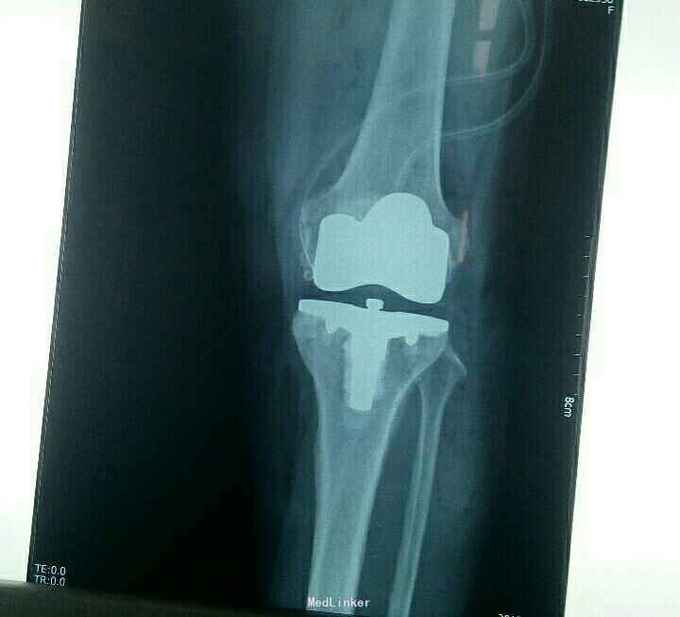

右膝骨性关节炎,行右侧人工全膝关节置换术,术后常规抗生素抗感染,丹参川芎嗪注射液活血化瘀,曲克芦丁脑蛋白水解物预防创伤性水肿,兰索拉唑预防应激性溃疡,低分子肝素抗凝,冰疗等

术后功能锻练,恢复良好,疼痛证状消失,下地行走。